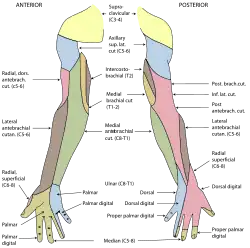

Nerve supply

The hand is innervated by the radial, median, and ulnar nerves.

- Motor

The radial nerve supplies the finger extensors and the thumb abductor, thus the muscles that extends at the wrist and metacarpophalangeal joints (knuckles); and that abducts and extends the thumb. The median nerve supplies the flexors of the wrist and digits, the abductors and opponens of the thumb, the first and second lumbrical. The ulnar nerve supplies the remaining intrinsic muscles of the hand.[15]

All muscles of the hand are innervated by the brachial plexus (C5–T1) and can be classified by innervation:[16]

| Nerve | Muscles |

|---|---|

| Radial | Extensors: carpi radialis longus and brevis, digitorum, digiti minimi, carpi ulnaris, pollicis longus and brevis, and indicis. Other: abductor pollicis longus. |

| Median | Flexors: carpi radialis, pollicis longus, digitorum profundus (half), superficialis, and pollicis brevis (superficial head). Other: palmaris longus. abductor pollicis brevis, opponens pollicis, and first and second lumbricals. |

| Ulnar | Flexor carpi ulnaris, flexor digitorum profundus (half), palmaris brevis, flexor digiti minimi, abductor digiti minimi, opponens digiti minimi, adductor pollicis, flexor pollicis brevis (deep head), palmar and dorsal interossei, and third and fourth lumbricals. |

- Sensory

The radial nerve supplies the skin on the back of the hand from the thumb to the ring finger and the dorsal aspects of the index, middle, and half ring fingers as far as the proximal interphalangeal joints. The median nerve supplies the palmar side of the thumb, index, middle, and half ring fingers. Dorsal branches innervates the distal phalanges of the index, middle, and half ring fingers. The ulnar nerve supplies the ulnar third of the hand, both at the palm and the back of the hand, and the little and half ring fingers.[15]

There is a considerable variation to this general pattern, except for the little finger and volar surface of the index finger. For example, in some individuals, the ulnar nerve supplies the entire ring finger and the ulnar side of the middle finger, whilst, in others, the median nerve supplies the entire ring finger.[15]